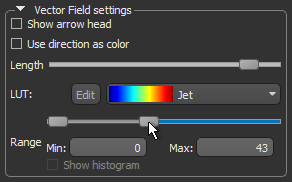

- Uncheck the Show arrow head option. This usually improves the visibility of the vectors in the field.

- Use the Length slider to adjust the length of the vectors.

- Choose another look-up table (LUT) in the LUT drop-down menu.

NOTE The Jet LUT is often a good color scheme choice. In this LUT, vectors corresponding to the highest surface anisotropy are colored red, while those corresponding to the lowest, or are isotropic, are colored blue.

- Threshold the vector field-based map to show only high or low anisotropy areas with the Range slider, as shown below.

The thresholded map shown below shows only low anisotropy areas located near articulating surfaces.